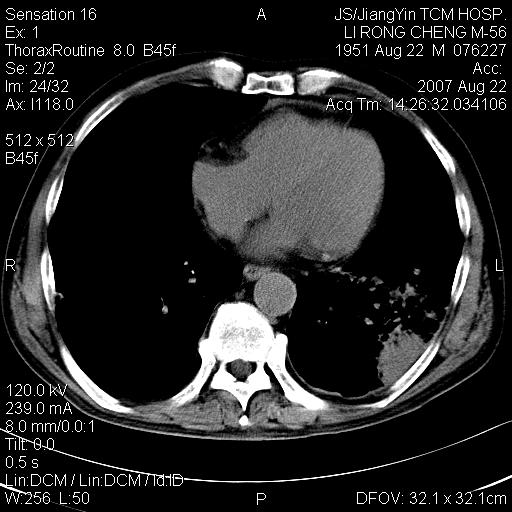

标题: CT9479:M,56Y,DM病史,咳嗽发热5天.肺脓疡.肺癌? [打印本页]

标题: CT9479:M,56Y,DM病史,咳嗽发热5天.肺脓疡.肺癌?

左下肺炎性病变,有支气管扩张,考虑肺结核合并感染。

左肺下叶支气管呈小囊状扩张。下叶背段有类圆形高密度影,边缘模糊,外与胸膜相连。左侧胸膜增厚粘连。心包膜增厚。结合病史考虑1支扩并感染2胸膜及心包炎。

左下肺团片状类软组织密度影,形态不规则,边缘欠规整,其内可见液化区及气体影,病灶内侧见引流支气管影,相邻胸膜反应性增厚。病灶周围肺野内见增粗支气管,壁厚,边缘模糊。考虑:支气管扩张并感染;肺脓肿。

肺结核;肺内感染性变;支气管扩张;胸膜增厚。

考虑左下肺感染,脓肿形成,左下肺支气管扩张,左侧胸膜增厚。其他待排,治疗复查

左肺下叶支扩合并感染,肺脓肿形成